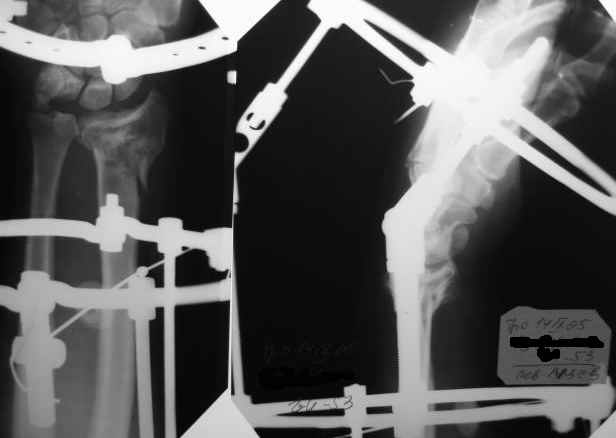

Спасибо, коллеги, за помощь в принятии решения. Остановились на АВФ, но в классической компоновке (3 секционный, замкнутые кольца). Снимки конечного результата в приложении.

Интраоперационно старались добиться более лучших взаимоотношений, но выяснилось (благо больной под региональной анестезией!), что у пациента был <перелом луча> с обеих сторон около 20 лет назад, движения на оперируемом суставе были несколько ограничены. Поэтому решили оставить так. К сожалению, снимков 20-ти летней давности не нашли. Планирую оставить внешнюю фиксацию на весь срок. Жду комментарии. С уважением, А.Минервин.